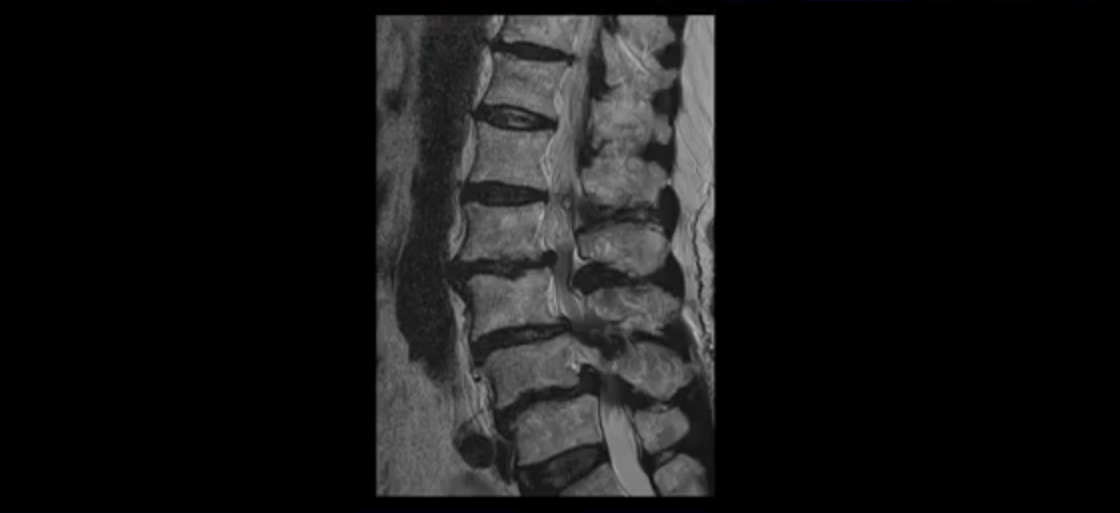

이 환자분 MRI를 보면서 더 자세히 설명 드리겠습니다. 이분은 허리의 다섯 마디가 다 안 좋은 환자분입니다. 84세 고령의 나이에 이렇게 여러 마디가 안 좋으면 대학병원에서도 수술이 어렵다는 얘기를 듣는 경우가 많습니다. 또 수술을 하더라도 결과가 안 좋을 수 있다는 얘기를 들을 가능성이 높습니다.

보시다시피 허리 다섯 마디 전부가 다 퇴행되어 있고,

두 마디에 전방전위증이 있고,

2번 3번,

3번 4번,

4번 5번에 중심성 협착이 심하고

거의 모든 추간공 즉, 신경가지가 좌우로 빠져나가는 구멍이 다 좁아져 있습니다.